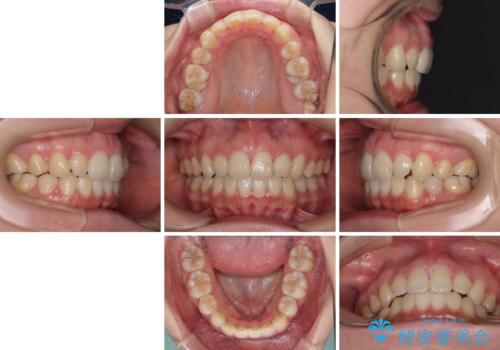

- 口元の突出感を気にして来院された患者様です。

診断の結果、上顎左右第一小臼歯4本抜歯により、叢生を解消するとともに口元を引っ込めていくことが望ましいと判断しました。

抜歯矯正による口元の改善にはワイヤー矯正が望ましいのですが、ダンサーとしての仕事を行っているため、インビザラインにて治療を行うこととしました。

インビザラインによる矯正治療は、どれだけマウスピースを外す時間を短くできるかが成功の鍵となりますが、抜歯矯正ではよりシビアに要求されます。

こちらの患者様は、1日22時間以上を厳守してくださり、3年強で終えることができました。